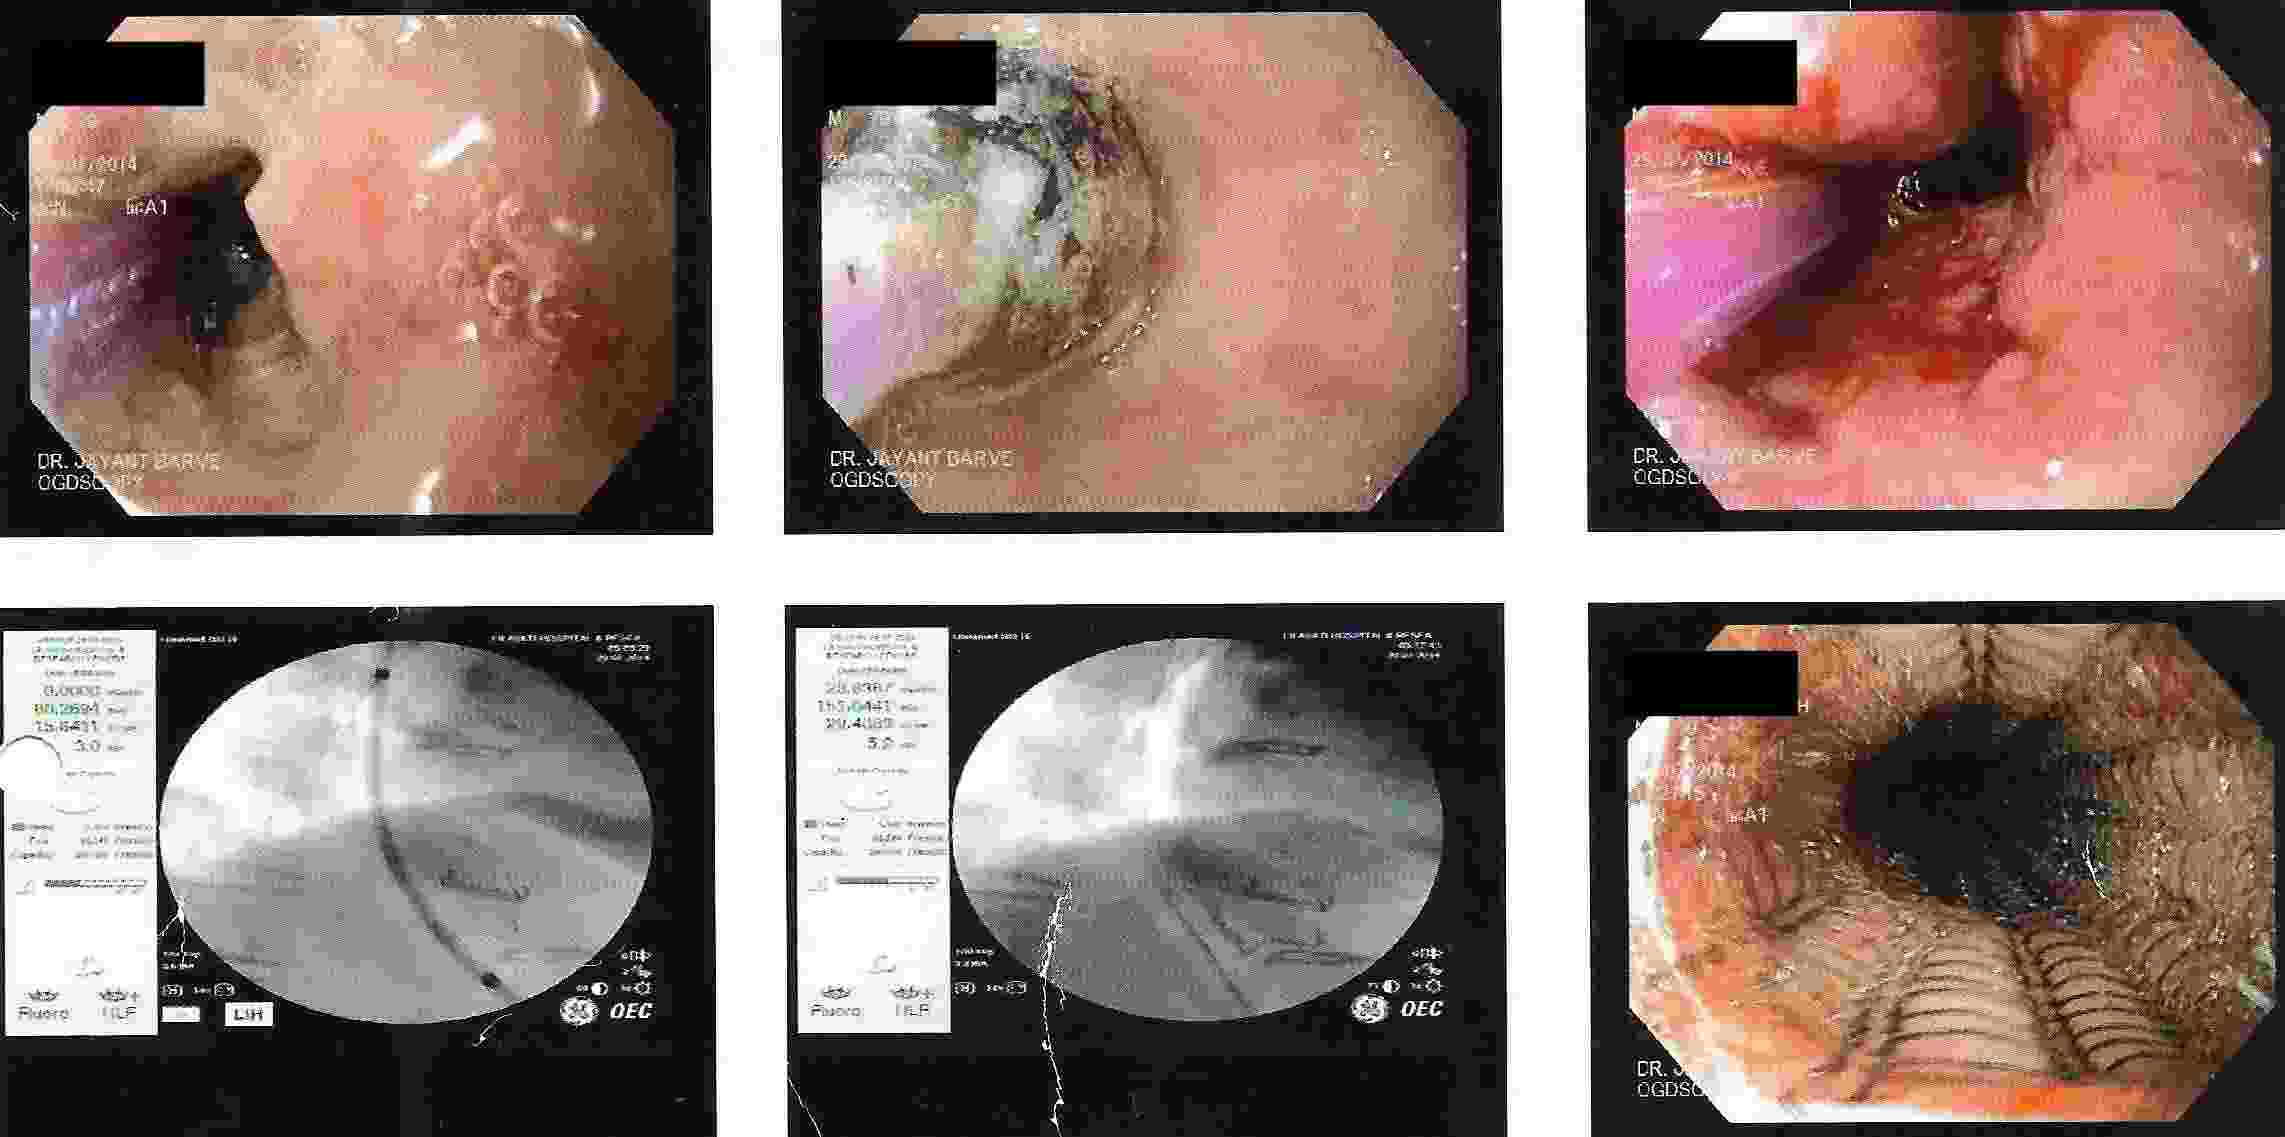

GALL BLADDER STONES TREATMENT

Endoscopic Retrograde Cholangio Pancreatography is an advanced endoscopic procedure related to

diseases of pancreas and biliary tree. Common indication for ERCP is jaundice due to obstruction

of biliary tube, which drains the bile from the liver into the intestine.

Obstruction can be due to a gallstone, which has slipped into bile tube and has blocked the bile tube.

These Stones can be removed by ERCP, without any surgery being involved.

This procedure is necessary if the patient has stones in the gallbladder and also in bile tube and

is always performed before Laparoscopic removal of gallbladder. Cancer of the gallbladder, biliary tree, pancreas,

duodenum or obstruction by lymph nodes can be responsible for jaundice and can be very effectively

treated by ERCP without any need for surgery.

This technique is important in these conditions as majority of the patients coming for jaundice are at an advanced stage of cancer and need palliative treatment to give relief from severe itching and jaundice. Infection or narrowing in the biliary tree can be treated by ERCP.

Common Biles Duct Stones

Common Biles Duct Stones

Cancer of the Bile Tube in Duodenum

Impacted Stone in Common Bile Duct

Chronic Pancreatitis is condition which can result in recurrent attacks of persistent and severe pain.

This can be due to presence of stones or narrowing of the pancreatic duct and can be treated by ERCP.

Pancreatic pseudocyst / collection of fluid is a complication of pancreatitis, which results

in abdominal pain, vomiting, fever etc. It is a serious condition which can be treated by ERCP.

Treatment of Chronic Pancreatitis by Stent

Most of the lesions of biliary system and pancreas were treated earlier by surgery with its own complications, but now with ERCP these conditions can be treated without any surgery and morbidity and mortality related to surgery, and as a cheaper option for surgery and has become treatment of choice for the same.